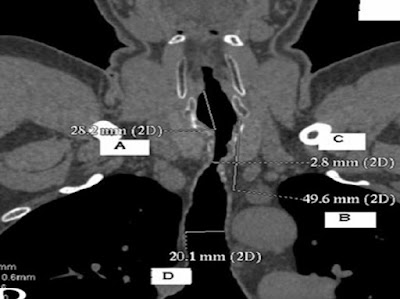

Radiological investigations

Plain films – Neck and chest

CT

MRI

Ultrasonography